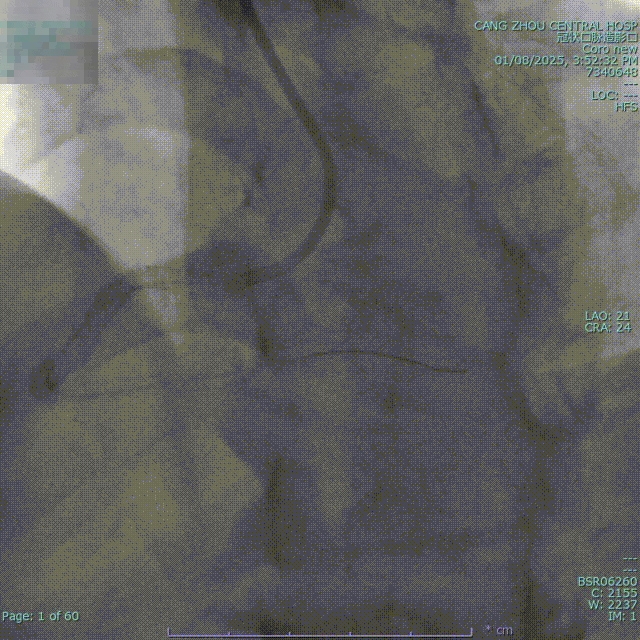

造影显示

1.LM未见明显狭窄;

2.LAD 支架术后,原支架通畅;

3.LCX支架术后,原支架通畅;

4.RCA:支架术后,支架内完全闭塞;

5.RCA优势型。

结论:三支病变,RCA支架内闭塞。

综合考虑后决定对右冠进行介入治疗。